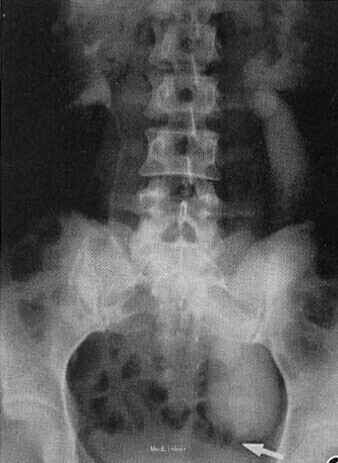

患者,女,36岁。1年前在外院B超提示:左侧输尿管上段扩张,左侧肾盂积水。近来感左侧腰部胀痛来院就诊。

彩超提示:左肾结石伴左肾中度积水;左输尿管全程囊状扩张。X线平片:两肾区、输尿管及膀胱区域内未见不透 X线结石影及异常钙化影。静脉肾盂造影(IVU):静脉注射76%泛影葡胺40ML 后,分别摄7min ,15min两肾区加压片,右侧肾盂、肾盏显影正常;左侧肾盏轻至中度扩大、积水,左肾盂未见显影。解压后 30min、50min ,90min各摄片,右侧输尿管对比剂排泄顺利,左侧肾盂、上段输尿管直至盆腔段输尿管对比剂由淡变浓自上而下缓慢充盈,左侧肾盂、输尿管全程扩大积水。120min摄片;左侧输尿管入膀胱处见一长约2cm狭窄段,近狭窄处输尿管管腔扩张明显,宽径5.2cm。IVU报告:左侧巨输尿管及左侧肾盂肾盏中度扩大积水。

左侧巨输尿管及左侧肾盂肾盏中度扩大积水。手术切除狭窄段输尿管并重建输尿管与膀胱接口。